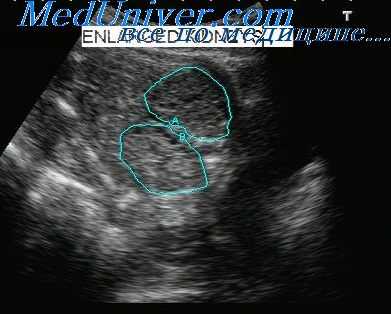

Удвоение почек плода

Удвоение собирательной системы почек является довольно распространенной аномалией, которая в отличие от других аномалий мочевыводящих путей, поражает девочек значительно чаще, чем мальчиков. В 83-90% случаев эта аномалия носит односторонний характер. Когда возникает полное удвоение мочеточников, верхний мочеточник обычно имплантируется эктопически, смещаясь каудально или медиально, и часто подвергается обструкции, а в нижнем мочеточнике, отходящем ортотопически может возникать рефлюкс.

Если верхний (эктопический) мочеточник также эктопически имплантируется в мочевой пузырь, может формироваться уретероцеле (эктопическое уретероцеле), пролабирующее в полость мочевого пузыря.